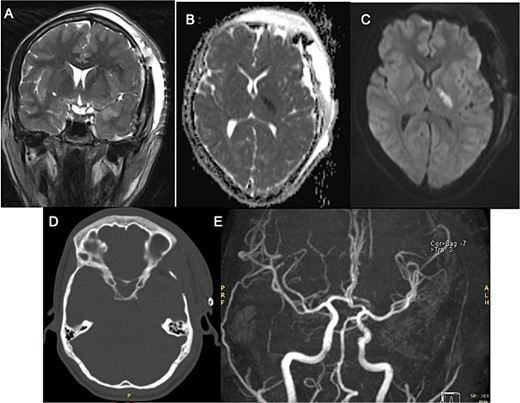

In the initial assessment of painless oculomotor palsy, brain MRI revealed a small, rounded lesion adjacent to the left posterior clinoid process (Fig. 1). Subsequent angiography (MRA) was performed due to suspicion of vascular pathology, confirming a well-defined lesion with low signal intensity in both T1 and T2 sequences. Post-contrast T1-weighted images demonstrated thin peripheral enhancement around the lesion. Aneurysms were ruled out by MRA, and a follow-up head CT scan identified a calcified lesion on the left posterior clinoid process extending into the interclinoid ligament, situated adjacent to the left oculomotor cistern. Additionally, diffuse calcification of the interclinoid ligaments was observed on CT imaging.

Pre-surgical MRI (A–C) showing the presence of a lesion with low signal intensity on T2-weighted sequences (A, B) of 0.7 × 0.6 cm adjacent to anterior clinoid process and tents, concerning the oculomotor left cistern, with peripheral enhancement in post-contrast sequences (C) contacting the left third cranial nerve. No evidence of aneurysms in angiogram MRI (D). Head CT scan (E) with a calcified exophytic lesion concerning the left anterior clinoid.